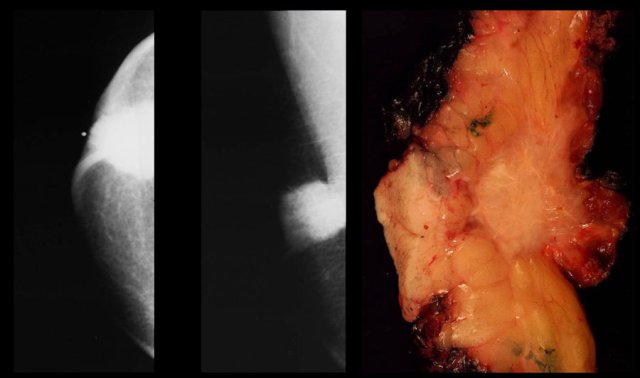

Epidermal inclusion cyst. T2WI with fat sat and pathology Epidermal inclusion cyst. T2WI with fat sat and pathology

On the left a T2W image demonstrating the cystic nature and the pathology specimen.